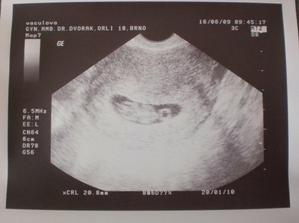

Náš drobeček...

focení v 33t.tt :-